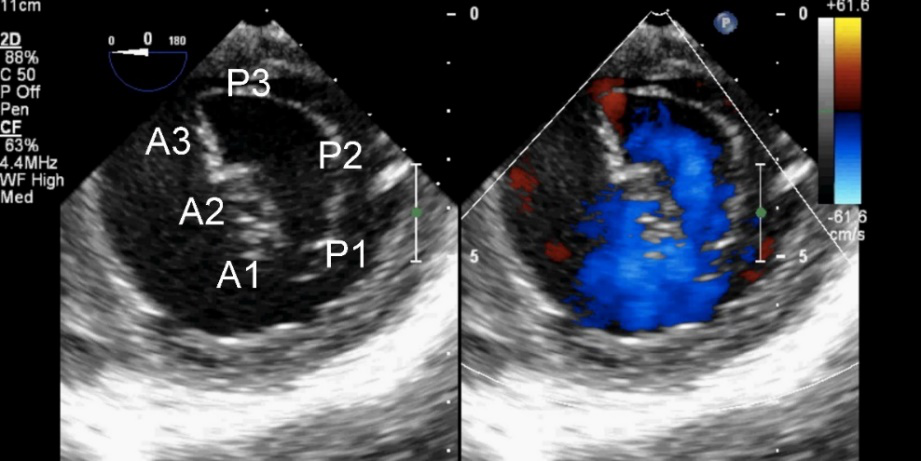

TEE切面可用来评估二尖瓣系统的每一部分,检查时将探头送至食管中段,操纵探头调整成像的角度使声平面对准二尖瓣环中心,探头晶片置于0~10度食管中段4腔心切面后开始旋转声平面,依次获得食管中段二尖瓣交界切面、食管中段左心室2腔切面、食管中段左心室长轴切面,在各个标准切面上可以观察不同小叶的功能状态,各个小叶与标准切面的对应关系如下图所示。

图10 TEE评价二尖瓣形态和功能的基本切面(标注二尖瓣分区)

TEE切面与二尖瓣分区的对应关系可用于二尖瓣脱垂部位的判断,但要注意的是:一定要将2D或3D图像与二尖瓣模型对应起来,不理解切面和模型之间的空间关系,直接用文献上的分区对应实际的超声图像会导致定位不准和交流障碍(图11,12,13,14);另外,经胃底基底段短轴切面对诊断瓣叶裂和穿孔很有帮助,彩色多普勒可以提供有关反流束起源的信息(图14)。

表5不同二维TEE切面所显示的二尖瓣小叶分区

图11四腔心切面显示二尖瓣后叶P2区脱垂